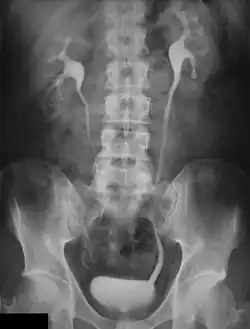

Pyelogram

An Example of an IVU radiograph

An intravenous pyelogram (IVP), also called an intravenous urogram (IVU), is a radiological procedure used to visualize abnormalities of the urinary system, including the kidneys, ureters, and bladder. Unlike a kidneys, ureters, and bladder x-ray (KUB), which is a plain (that is, noncontrast) radiograph, an IVP uses contrast to highlight the urinary tract.